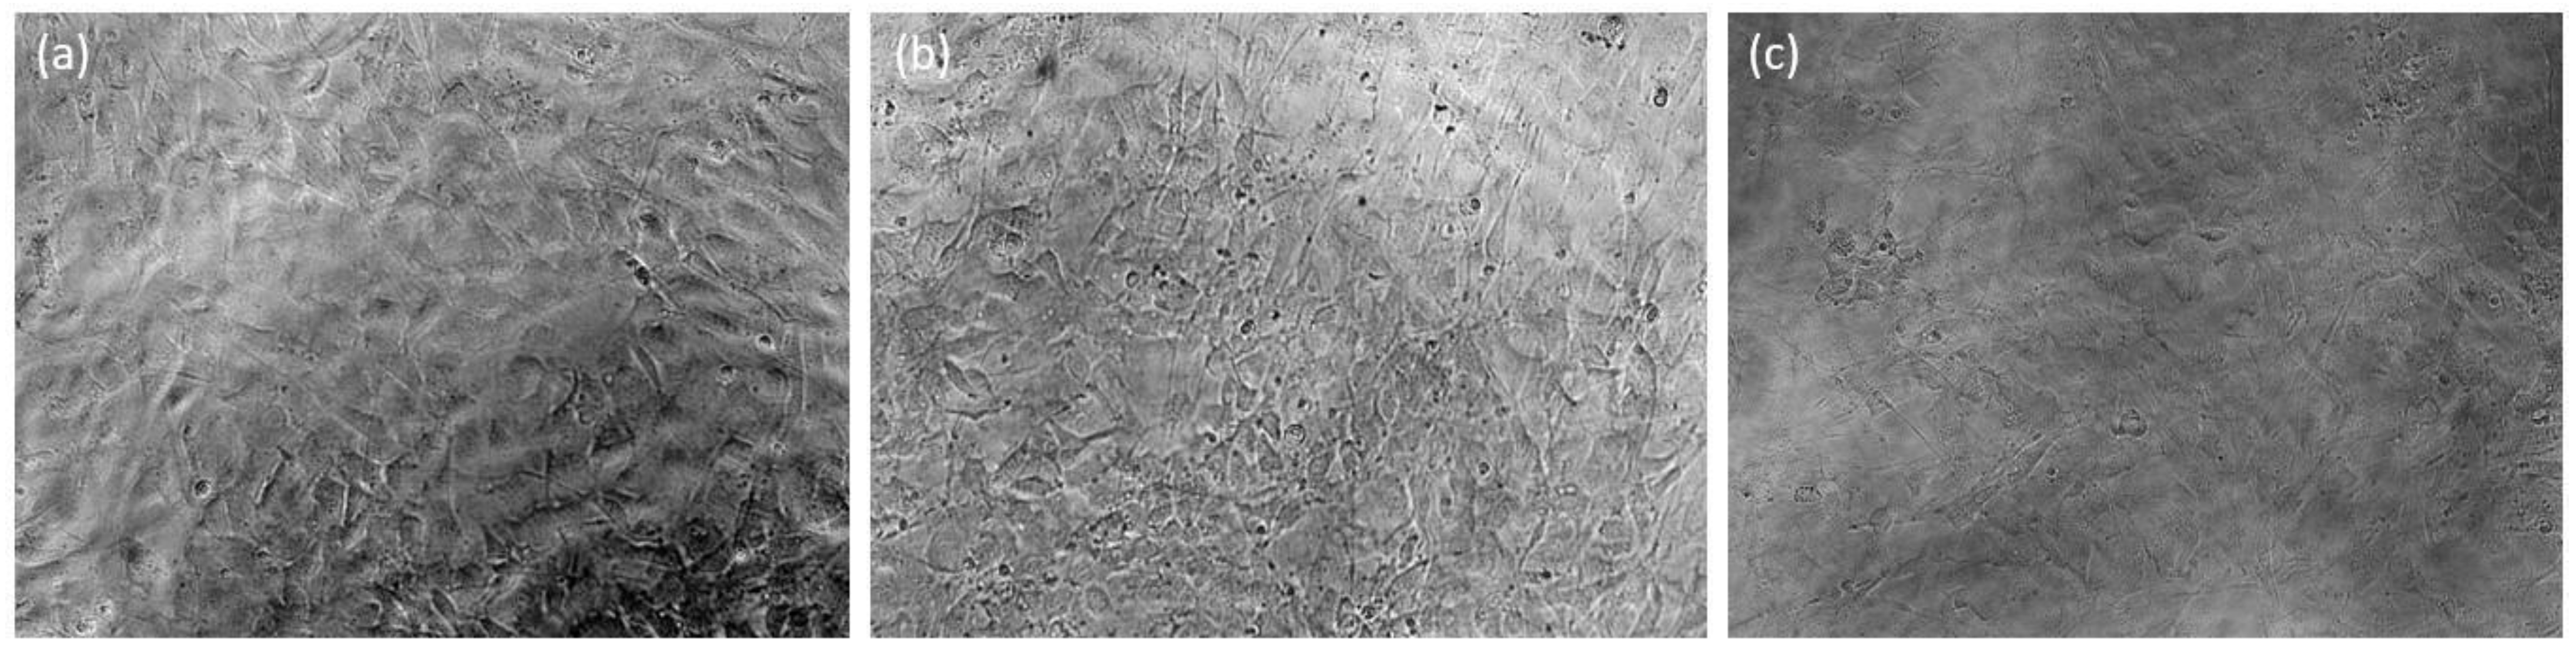

3.2.3. Morphological Analysis

3.3. Cytocompatibility Studies